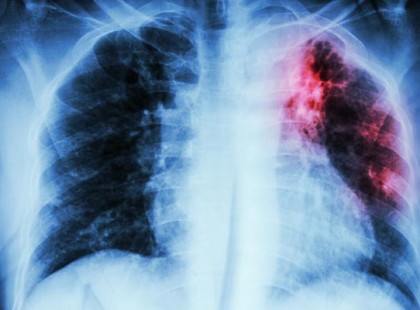

Vigyázat!!! Új tüdőbetegség pusztít a magyarok körében! Reggeli krákogással kezdődik az új halálos betegség! Veszélyesebb és alattomosabb, mint a tüdőrák!!!! Ezek a tünetek :

A rendszeres reggeli köhögést, krákogást és hirtelen kifulladást nem szabad félvállról venni, főleg ha az ember még...